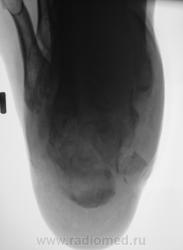

Лечение состояло из "множества рентгенов" и гипса. Срок - 5 месяцев.

Сейчас думают об остеомиелите.

Контуры пяточной кости относительно четкие, разрежение структуры пяточного бугра, в проекции перелома уплотнение структуры кости( имею в виду последние снимки).Клиника остеомиелита есть?

Во-первых, деформация пяточной кости; во-вторых, отсутствие консолидации, через некоторое время и ложный сустав сформируется. Неоднородное уплотнение костной структуры в теле кости может быть обусловдено как остеомиелитом, так и перераспределением нагрузки.

Признаков остеомиелита не вижу, только консолидир перелом с неуд стоянием отломков.